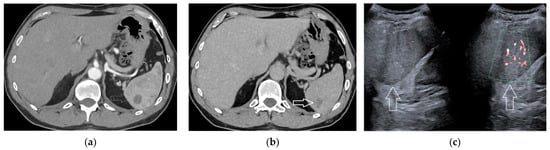

2.5. Hematoma and Abscess

2.6. Infarcts

2.7. Solid Lesions